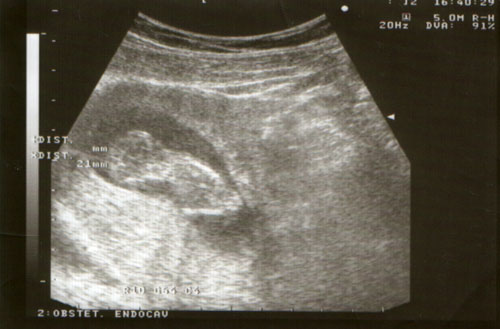

Ja a védőnő szeptember 28. írt a kiskönyvbe. +7 nap mínusz 3 hónap a szokásos módon számolta. Viszont a babanet kalkulátorra szept. 27. dobott ki.

Mind1 lehet, hogy 1 héttel hamarabb születik, mint Manó.